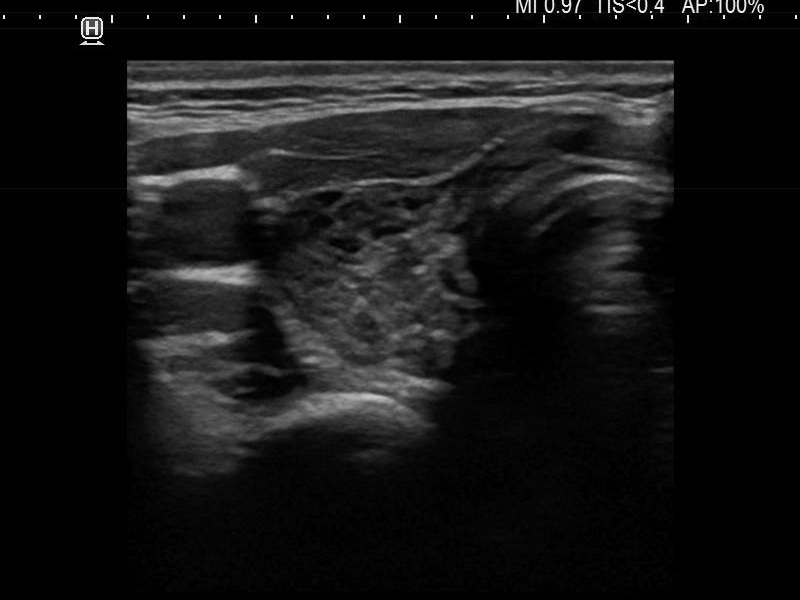

Ultrasonography. The thyroid was moderately hypoechoic and presented with numerous more and less hypoechoic discrete lesions. The largest of the latter was in the lower ventromedial part of the left lobe and had cystic areas and intranodular echogenic figures. The latter included typical comet tail artifacts, back wall cystic figures and some ambiguous small bright granules. The lesion showed both perinodular and intranodular vascularity. Compared with the former examination the nodule increased by 22% in volume. This difference is within the intraobserver variation.

Comment. Based on the presence of typical comet-tail artifacts, the questionable punctate echogenic granules are worth considering also colloid crystals.